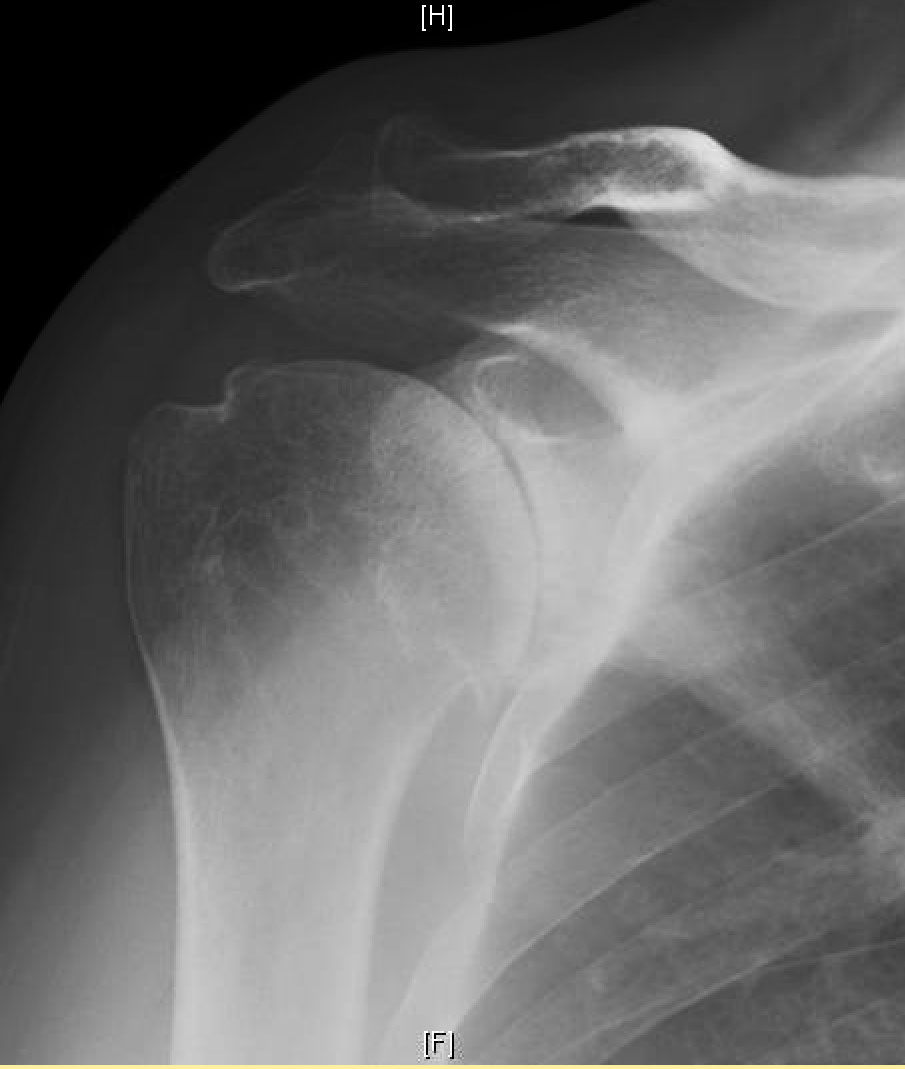

Shoulder Arthritis / Rotator Cuff Tears / Shoulder Pain Technological Shoulder Surgery Gone Wrong One of the more common rotator cuff problems is a tear of the tendon of the rotator cuff. Rotator cuff problems are a common cause of shoulder pain and difficulty with activities that require normal strength and mobility of the shoulder joint. Total shoulder replacement surgery is a complicated manipulation of the patient's native bone, prosthetics, and soft tissue. There. Shoulder Surgery Gone Wrong.